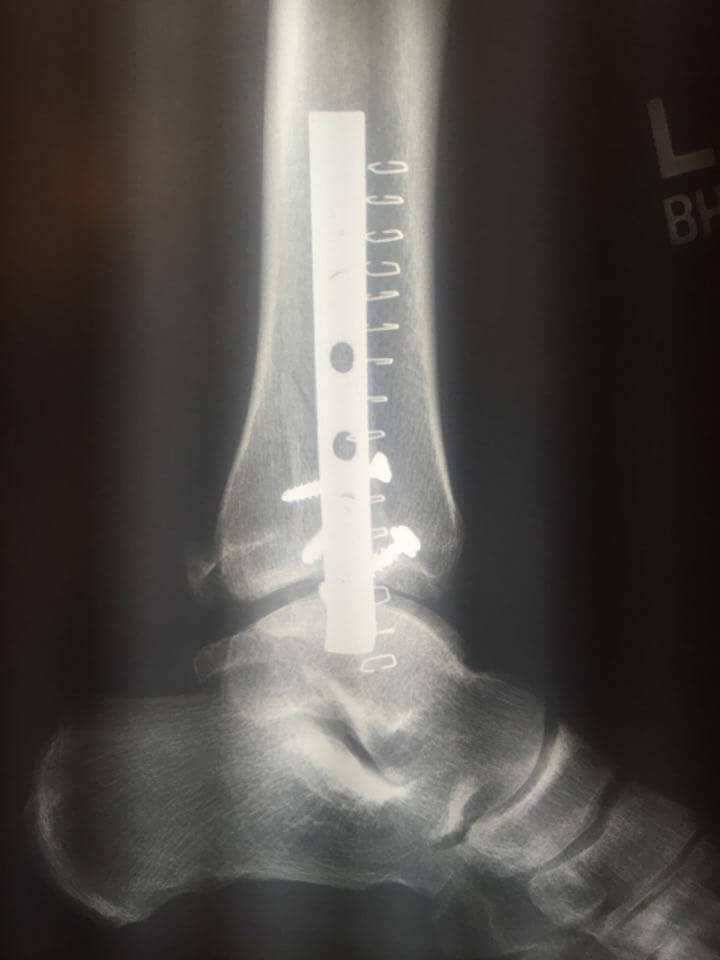

Mike has since had surgery and gotten some great new hardware for his ankle, which was broken in several spots – I’ll throw some X-Rays up if Mike is cool with it. He should be on a walking cast by August and we’re thinking of a late season paddle in October perhaps.